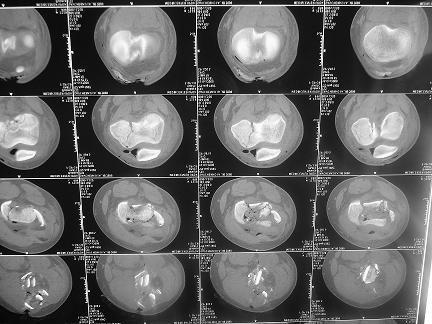

Тяжелый открытый внутрисуставной перелом дистальной части бедренной кости и открытый голени в средней трети,множественные раны и некрозы на голени. Что делать? 4 суток после мотоциклетной травмы. 16 лет. Переведен из районной больницы, где основные раны на голени и бедре были ушиты наглухо и наложено скелетное вытяжение за бугристость и пятку, через 2 суток. При поступлении - высокая лихорадка, анемия. Из сопутствующих только сотряс. Раны на бедре и голени расскрыты, обработаны. На передней поверхности бедра рана с начавшимся нагноением, около 15х8см, полость распространяется от места перелома, где значительная часть отломков практически лишена связи с мягкими тканями, до верхней трети, откуда удалена гематома 200мл. 4-главая мышца повреждена, отрыв и перелом без смещения надколенника. Проксимальный отломок бедренной кости на протяжении 20см на 2 трети окружности лишен надкостницы. Резко выраженный отек бедра. На голени рана на передней поверхности 12 х 5см, дном является лишенная надкостницы большеберцовая кость, некроз краев раны. Множественные раны и участки некрозов кожи в области коленного сустава, обширные некрозы на голени в нижней и верхней третях. Пульсация на стопе отчетливая, при этом некрозы в нижней трети голени постепенно увеличиваются. Сейчас на ИВЛ с клиникой респираторного дистресс синдрома. Что делать - неясно. Возможен ли при таком переломе бедра интрамедуллярный остеосинтез? Было бы здорово фиксировать оба перелома через 1 доступ.

Ситуация на сейчас довольно однозначно направляет намерения в сторону остеосинтеза бедра и голени bridging стержневым аппаратом, с повторными минимально травматичными обработками ран. Раны хорошо бы закрывать с помощью VAC. На форуме эту технику не раз обсуждали. Она реализуется необязательно только с фирменными поролоном, пленкой и отсосом KCI. Окончательную внутреннюю фиксацию планировать уже после разрешения проблем с легкими и мягкими тканями. Лучше бы посмотреть не только CT, но и обычные рентгенограммы а протяжении. Может быть, и интрамедуллярный остеосинтез уместно будет обсудить.

Больному с политравмой установлен наружный "spanning-bridging" фиксатор, после нескольких Irrigation&Debridment на фоне отрицательного посева из раны, через открытый участок установлен 4.5 mm Locking Plate.

На фоне фиксированного перелома бедра мероприятия по восстановлению мягкотканого покрова. Перелом голени зафиксирован после стабилизации бедра традиционным методом.